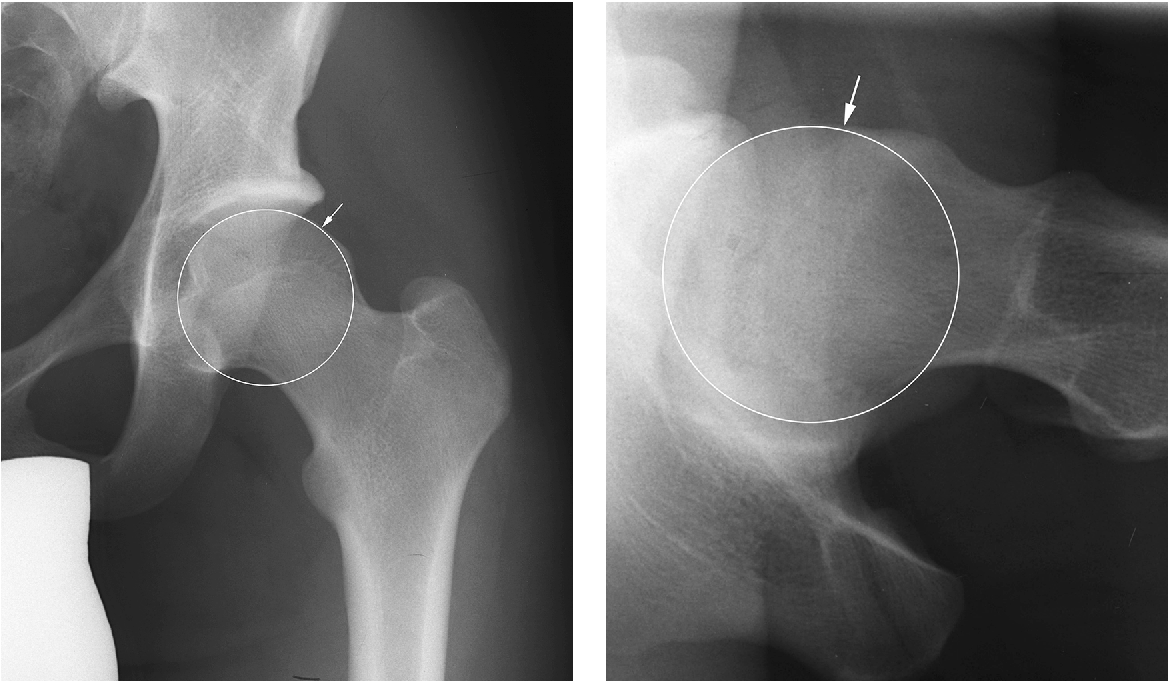

1.CAM-тип

Нарост (бугорок) или утолщение на бедренной шейке/основания головки, что делает её не идеально сферической. При сгибании/вращении бедра это утолщение «входит» в вертлужную впадину и травмирует край впадины или губу.

- Рентгенография: выявление морфологии, утолщения, изменения формы.

- МРТ / МР-артрография: оценка состояния хряща, губы, мягких тканей, наличие сопутствующих повреждений.